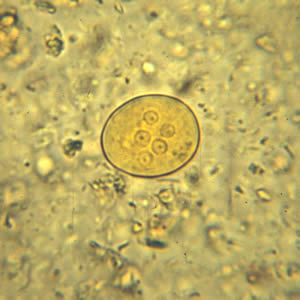

E.histolytica cyst

four nuclei and a chromatoid body with blunt ends